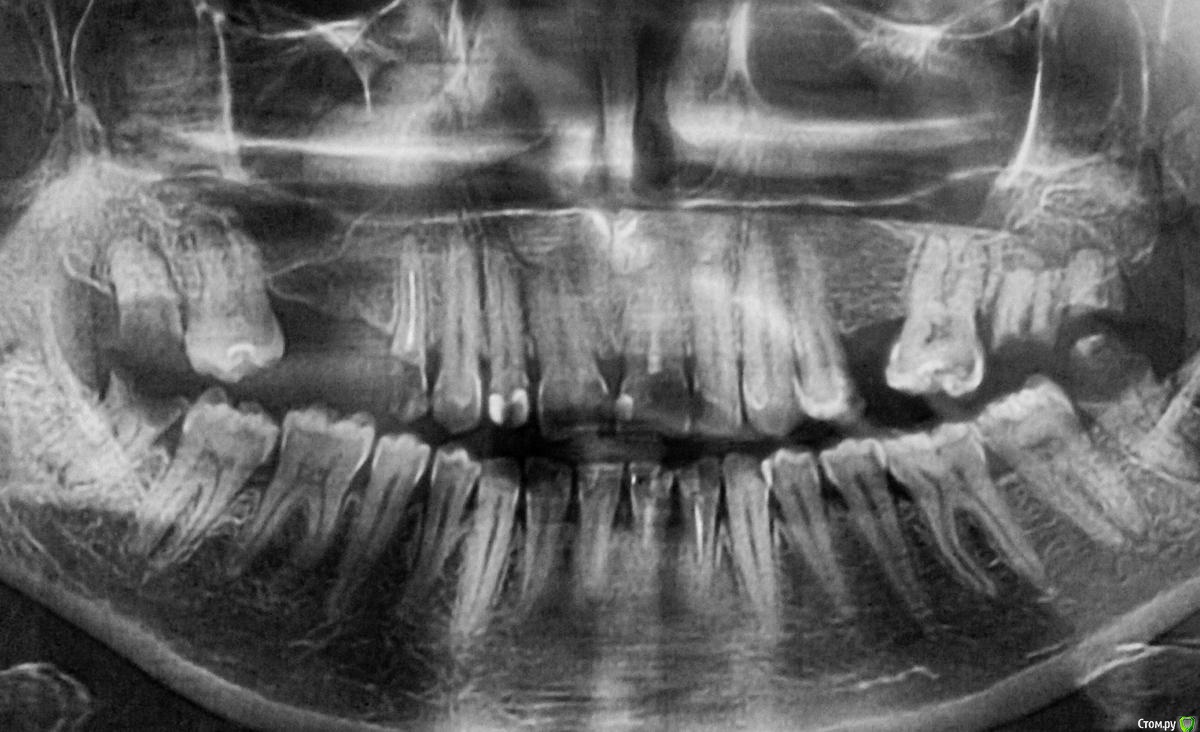

Mari475 Опубликовано 7 февраля, 2015 Поделиться Опубликовано 7 февраля, 2015 Добрый день! Помогите, пожалуйста, разобраться... Мой стоматолог сказал, что надо ставить мост на 4 верхних резца, а когда пригласили протезиста, он сказал, что надо делать дугу "от 6 до 6"... К слову: 21 зуб удалили. Сказали, что надо удалять еще 6 зубов (4 верхних и 2 нижних). Знаю, что зубы плохие и сама в этом виновата, но в данный момент не понимаю, как должно быть правильно, если действительно надо дугу ставить, то буду ставить. Заранее спасибо за ответ/совет! Ссылка на комментарий